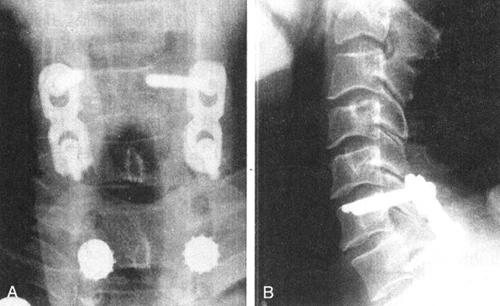

五、颈椎侧块钢板固定

各种不同的钢丝技术已应用于颈椎后路融合多年。这些方法通常在术后需要头环背心、石膏等外固定支持直至骨性愈合。与钢丝固定技术相比,颈椎关节突侧块螺钉钢板技术可以提供更为确实的内在稳定性。侧块钢板固定的优点包括:操作简便、对后结构的完整性依赖小、可获得更强的即刻稳定性。特别对颈椎后柱多节段遭到破坏或不稳时,后路侧块钢板固定远较颈椎棘突间钢丝固定术的效果好得多,固定更坚强,缩短术后的外固定时间。鉴于上述优点,侧块钢板得到了较为广泛的应用。70年代末,Roy-Camill首次将钻铬锡合金钢板应用于颈椎侧块固定。Magerl将原来的侧块钢板改良,在钢板下端带一钩(带钩钢板)钩在下一椎板的下缘,以防止钢板的上下移动。1989年,Haid将其发展为钛合金植入物,钛合金在X线和MR成像时的伪影均小于不锈钢,故它的应用得到了较大的发展。由于钛合金的生物相容性均十分良好,故内植物均无需拆除。目前常见的有ASIF的重建钢板及Cervifix(棒系统)、Sofamor的Axis(板系统)(图13-24A)、Vertex(棒系统)(图13-24B)、Depuy的PEAK(有棒系统,也有板系统)等(图13-24C、D)。

图13-23 48岁女性C1爆裂骨折,枕颈及C1~C2关节不稳。做后路枕颈固定,镶嵌植骨。枕骨用双皮质螺钉,C2为椎弓根钉

图13-24 各种侧块固定系统(A.B.Sofamor的Axis和Vertex;C.D.Depuy的PEAK)